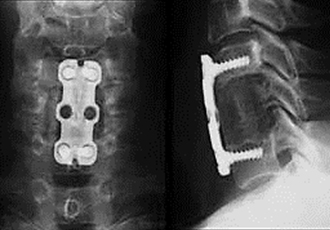

1. 側弯症手術

背中側を切開して椎骨の後方に椎弓根スクリューという金属を挿入して変形を矯正する手術を行います。椎弓根スクリューによる変形矯正は従来の方法に比べ良好な矯正が可能です。ナビゲーションシステムを導入して、正確に椎弓根スクリューを挿入できるように安全対策を行っております。また手術中は常に脊髄に電気を流し、脊髄神経の障害が起きていないかをリアルタイムに確認できる脊髄モニタリングも行いながら手術を行っており、手術治療の安全性はかなり高くなっております。

症例:特発性側弯症